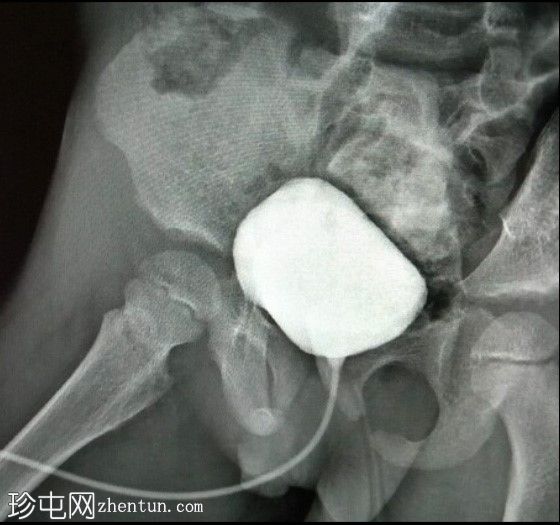

正位

斜位

初步影像显示直肠气体影正常;未见骨骼或关节异常。膀胱充盈度中等;轮廓光滑,未见小梁、囊状结构或憩室。

侧位影像显示膀胱后方可见一管状结构,可能为阴道,且充满造影剂。这提示膀胱与阴道之间存在共同的会阴开口。然而,这些影像并未显示该结构之间的瘘管连接。